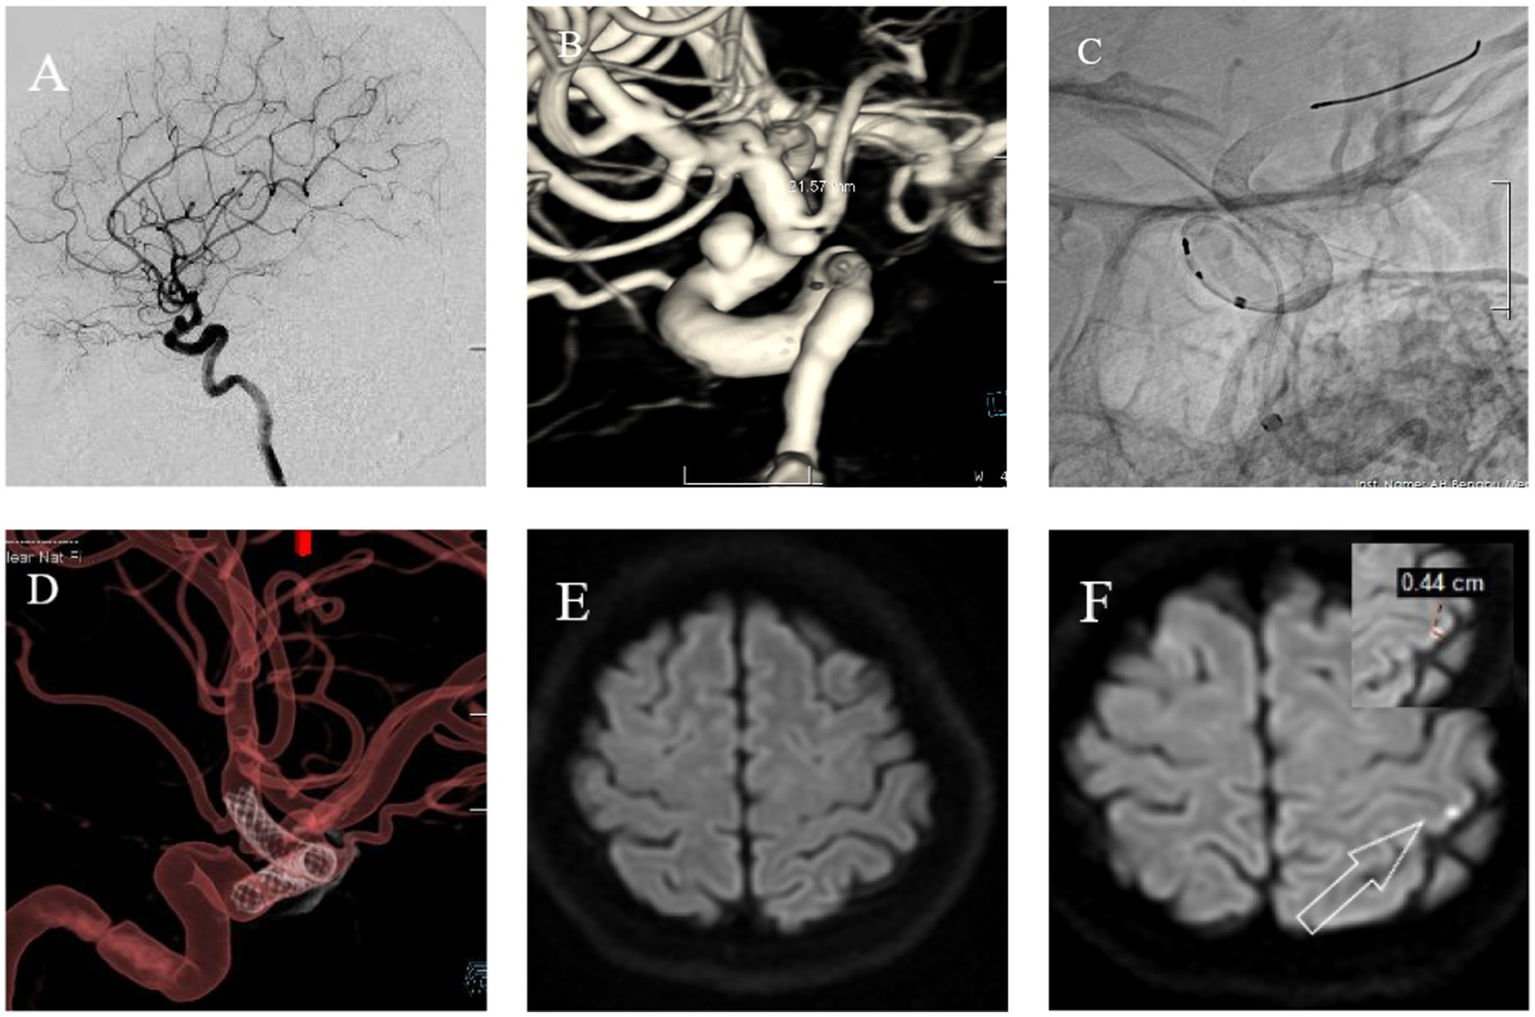

The following brief descriptions of cases of postoperative microembolic infarction are based on clinical treatment and imaging data, as shown in Figures 3, 4.

Figure 3

A 71 year old female with headaches, dizziness, and transient fainting for half a month. (A) Cranial DSA showing the location of the intracranial aneurysm in the 2D plane during the operation. (B) Cranial DSA showing a 3D image of the left middle cerebral artery aneurysm. (C) Intraoperative 2D plane showing the placement of coils and stents. (D) Postoperative 3D plane showing the placement of coils and stents. (E) Preoperative MRI-DWI showed no new infarcts. (F) Postoperative MRI-DWI on day three showed an acute microinfarction lesion in the left periventricular region with a diameter of approximately 0.43 cm.